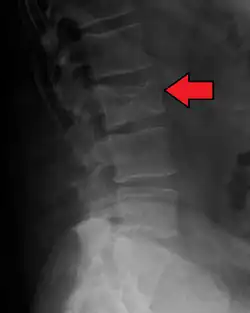

Pathological fracture of the lumbar spine due to multiple myeloma -

The diagnostic examination of a person with suspected multiple myeloma typically includes a skeletal survey. This is a series of X-rays of the skull, axial skeleton, and proximal long bones. Myeloma activity sometimes appears as "lytic lesions" (with local disappearance of normal bone due to resorption) or as "punched-out lesions" on the skull X-ray ("raindrop skull"). Lesions may also be sclerotic, which is seen as radiodense.[76] Overall, the radiodensity of myeloma is between −30 and 120 Hounsfield units (HU).[77] Magnetic resonance imaging is more sensitive than simple X-rays in the detection of lytic lesions. An MRI may supersede a skeletal survey, especially when vertebral disease is suspected. Occasionally, a CT scan is performed to measure the size of soft-tissue plasmacytomas. Nuclear Medicine Bone scans are typically not of any additional value in the workup of people with myeloma (no new bone formation; lytic lesions not well visualized on nuclear bone scan).

Bone pain affects almost 70% of people with multiple myeloma and is one of the most common symptoms.[2]: 653 [23] Myeloma bone pain usually involves the spine and ribs and worsens with activity. Persistent, localized pain may indicate a pathological bone fracture. Involvement of the vertebrae may lead to spinal cord compression or kyphosis. Myeloma bone disease is due to the overexpression of receptor activator for nuclear factor κ B ligand (RANKL) by bone marrow stroma. RANKL activates osteoclasts, which resorb bone. The resultant bone lesions are lytic (cause breakdown) in nature. They are best seen in plain radiographs, which may show "punched-out" resorptive lesions (including the "raindrop" appearance of the skull on radiography). The breakdown of bone also leads to the release of calcium ions into the blood, leading to hypercalcemia and its associated symptoms.[24]